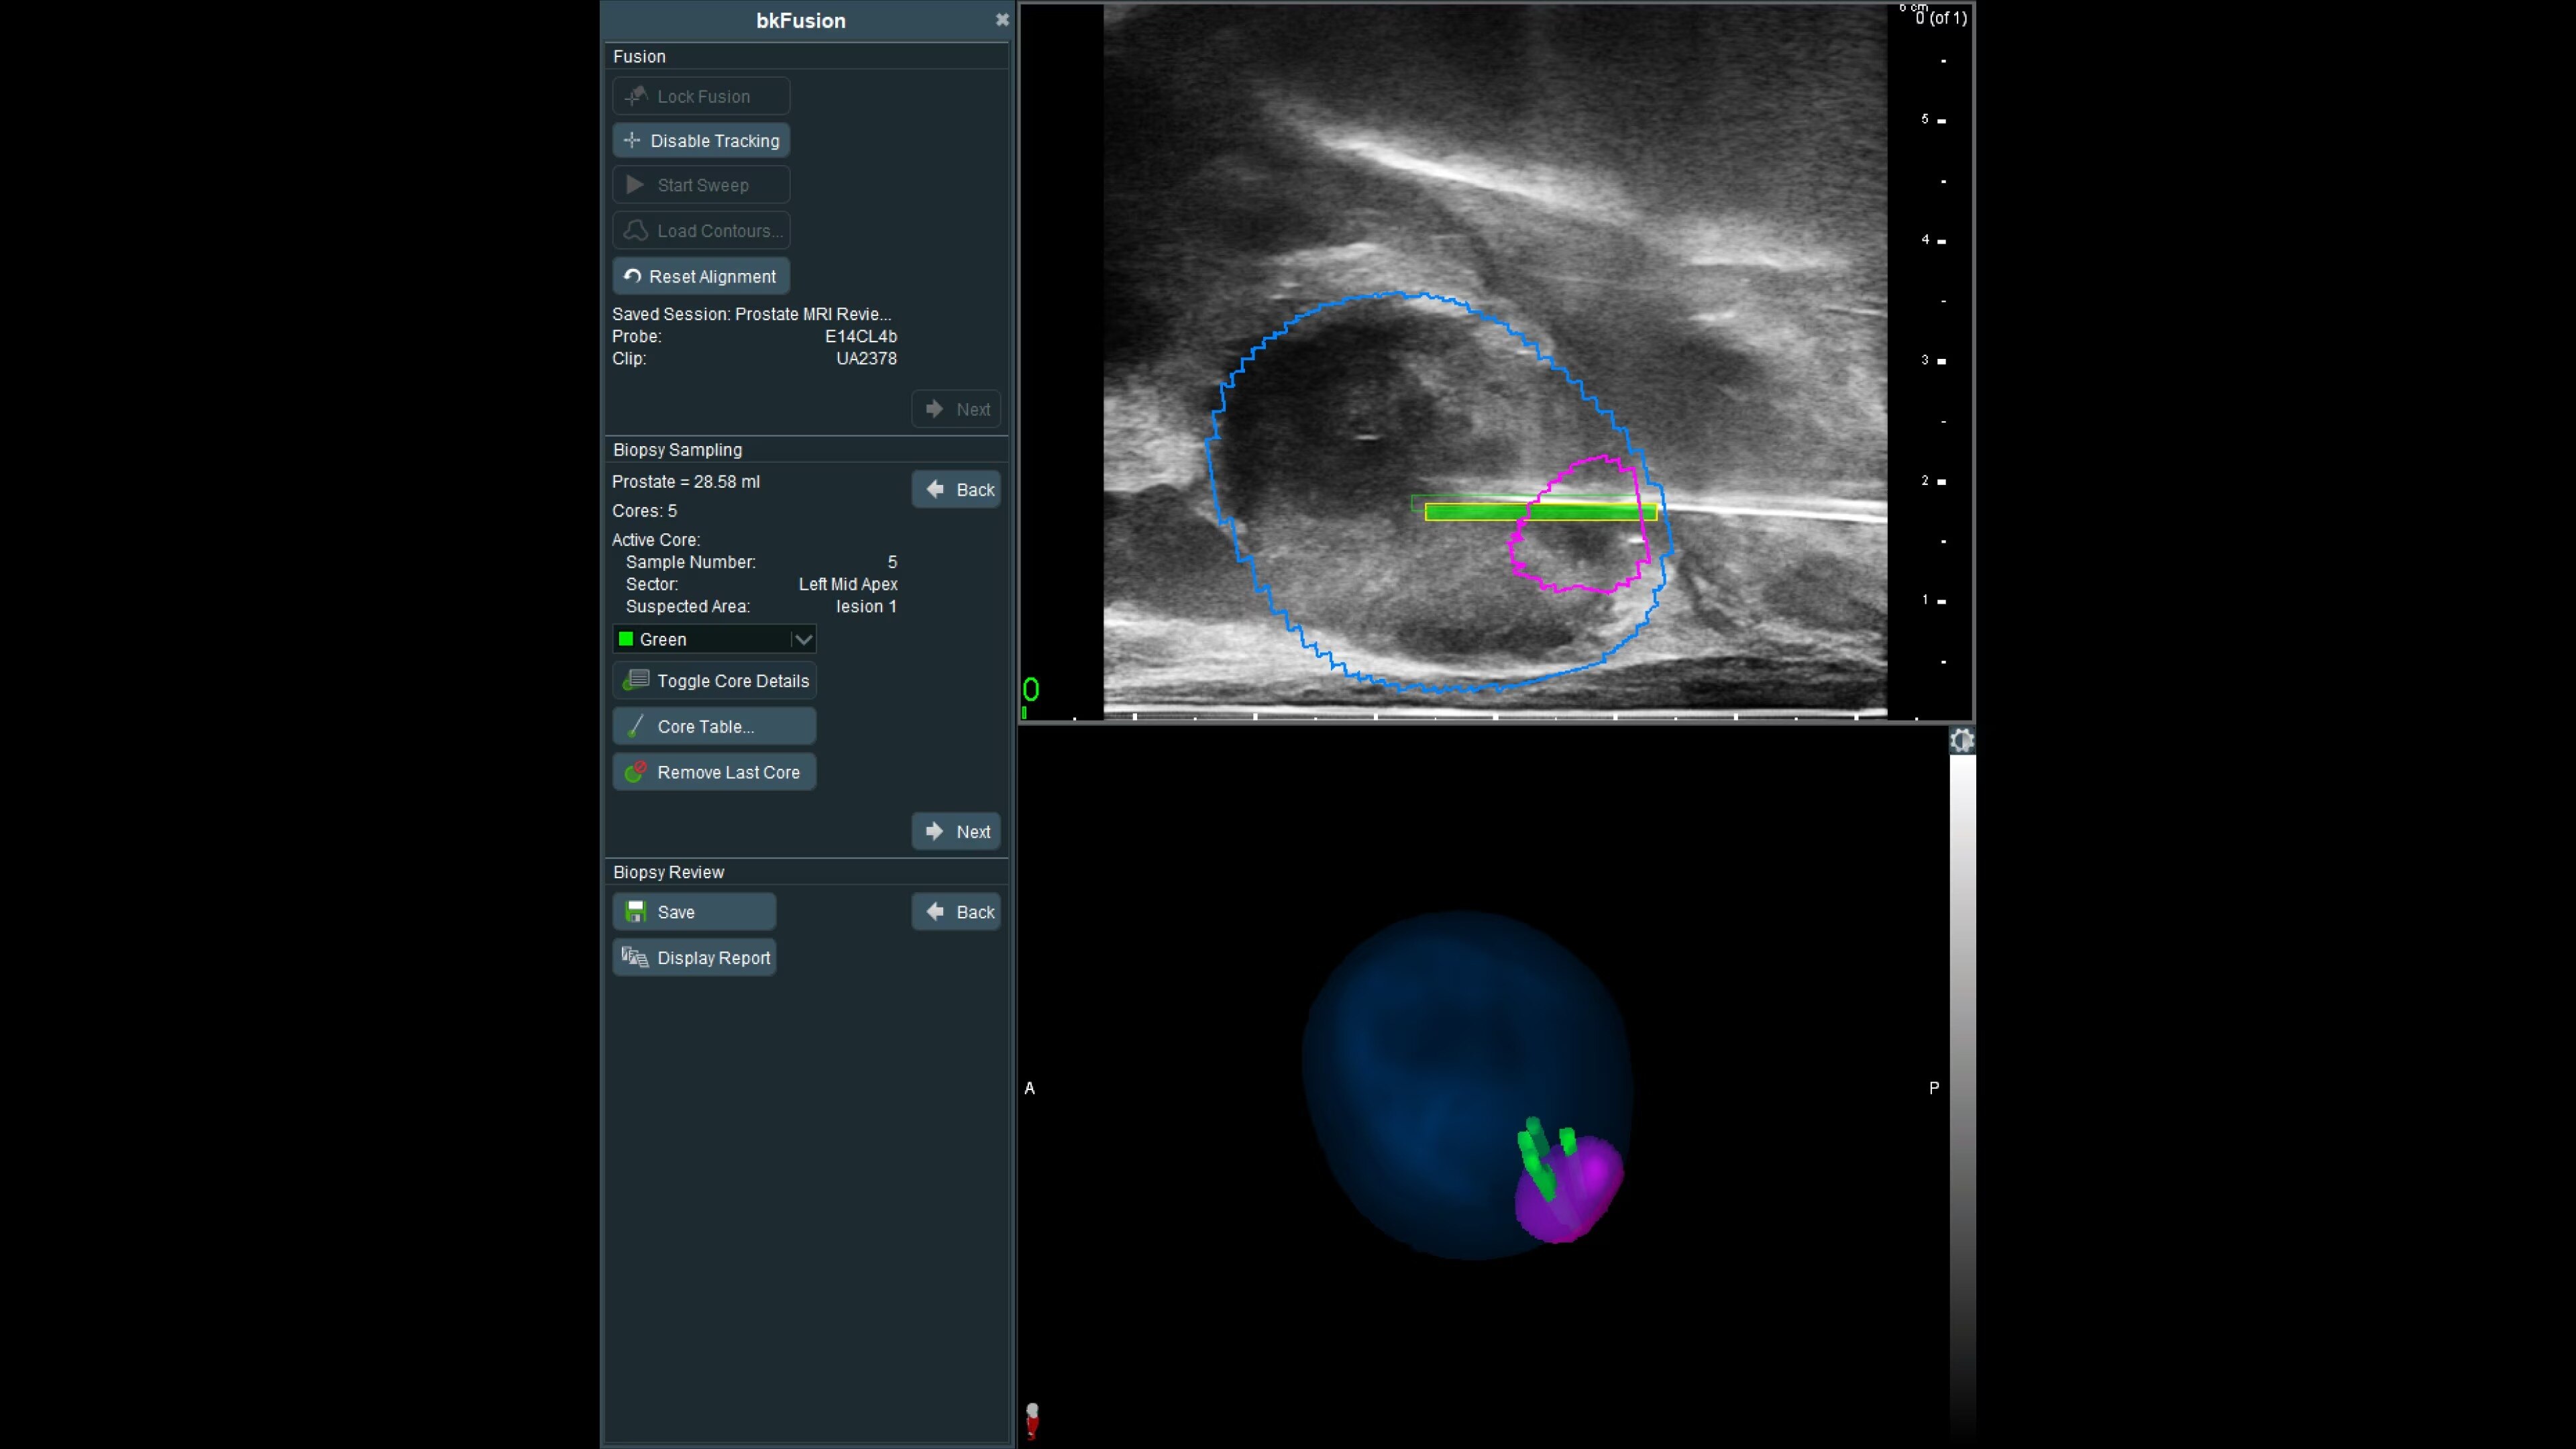

bkFusion evolves with your practice, offering transperineal stabilized and freehand, or transrectal endfire and sidefire techniques, supported by sterilizable transducers. The TP approach reduces infection risk and suits office or OR settings, showing high patient tolerability and negligible infection rates. Choose between freehand or stabilized approaches, with flexibility for office or OR settings.

Freehand transperineal biplane transducer

Achieve precise biopsies with the transperineal biplane transducer and navigation sensor. Requires electromagnetic (EM) tracking.

Transrectal sidefire/endfire

Efficient biopsies with triplane and high-resolution endfire transducers. Integrated into a familiar transrectal workflow, compatible with freehand procedures and EM tracking.